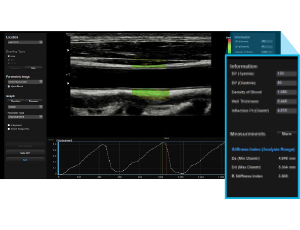

La fonctionnalité ArterialAnalysis™ permet l'évaluation morphologique (épaisseur intima-média) et fonctionnelle des vaisseaux. Cette technologie non invasive étudie dans toutes les directions, aussi bien axiale que longitudinale, la paroi des vaisseaux et contribue à la détection précoce de maladies cardiovasculaires.